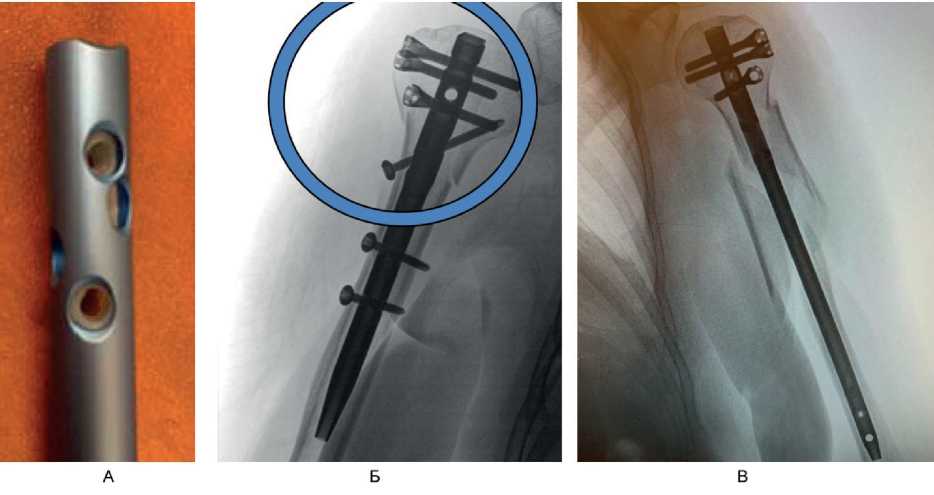

Благодаря конструктивным характеристикам штифты последнего поколения применимы при разном состоянии костной ткани и различных типах переломов. Так, для пациентов с низкой плотностью костной ткани их применение оправдано, поскольку данные штифты имеют в канале полипропиленовый вкладыш, который обеспечивает дополнительную стабилизацию блокируемых винтов (рис. 11А). В случае перелома хирургической шейки плеча (переломы типа В и С по классификации АО), когда отмечаются дефект по медиальной поверхности и оскольчатый характер перелома в калькарной области, требуется стабилизация латеральной и медиальной колонн. Применение современных штифтов в данной ситуации позволяет без технических трудностей добиться медиальной устойчивости, так как расположение самого штифта внутри канала обеспечивает стабильность латеральной и медиальной стенок плеча, к тому же полиаксиальное расположение винтов в головке плечевой кости и введение калькарного винта создают дополнительную опору в медальном отделе (см. рис. 11Б). При переломах хирургической шейки плечевой кости с расколом на диафизарную часть длинные версии штифтов позволяют применять малоинвазивную методику (см. рис. 11В).

Рис. 11. Интрамедуллярный штифт. А – полипропиленовый вкладыш внутри канала штифта; Б – медиальная стабильность обеспечена введением винта через штифт в калькарную область плечевой кости; В – длинная версия штифта